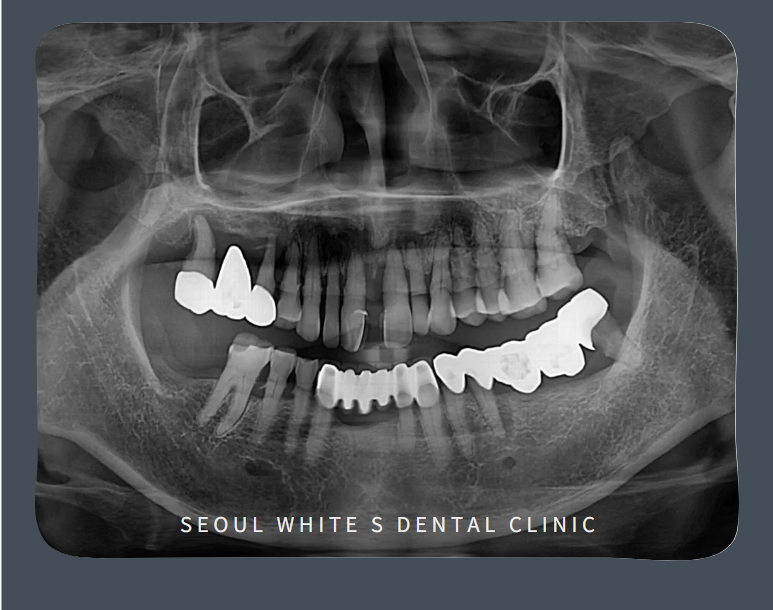

영도구치과잘하는곳 서울화이트S치과에 처음 내원하셨을 때 촬영한 사진입니다.위 앞니는 사이가 벌어져 있을 뿐만 아니라 작은 앞니까지 4개의 앞니가 살리기 어려운 상태였습니다.

오른쪽 어금니는 이전에 보철물을 하신 상태였는데,이미 치조골이 많이 녹은 상태로 흔들림이 심하여 발치가 불가피하였습니다.